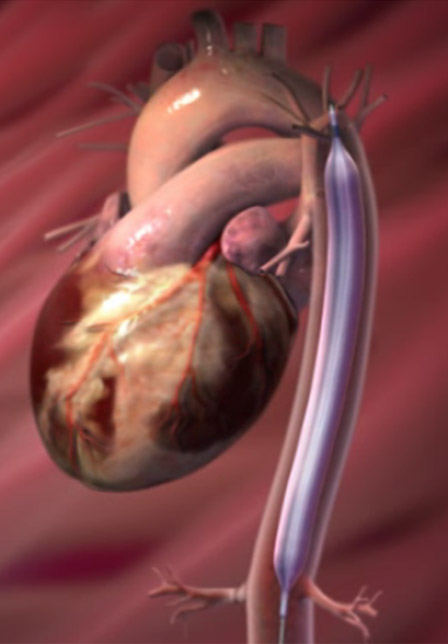

- IABP(大動脈内バルーンパンピング)

- Impella(補助循環用ポンプ)

機械的補充循環装置

下行大動脈内に挿入した大きなバルーンカテーテルを心拍動に合わせて拡張、収縮を繰り返すことによって心臓の補助を行う装置です。

補助循環用ポンプカテーテル(Impella)

左室から大動脈に血流を送り、循環補助、左室補助の役割を果たします。